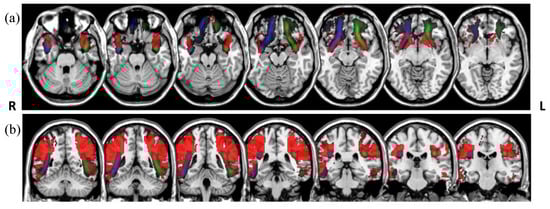

The Dice overlaps between the tract group maps (Figure 4) and the white matter atlas tracts are shown in Table 3. The group maps were created previous to the tract rejection during the visual assessment, and are therefore are unbiased by the rater’s manual intervention. We obtained moderate Dice overlaps for most of the tracts. To illustrate the mismatches, Figure 5 shows the tracts with the lowest overlap, bilateral arcuate, and uncinated fasciculi, created from the atlas-based reference tracts and an unsupervised model.

Figure 5.

Overlays of the uncinate (a) and arcuate (b) fasciculi. Atlas tracts represented in red (from [17]) and tracts segmented in the LBC1936 data using atlas-based reference tracts and unsupervised models in green (left) and blue (right), in radiological convention.

The Dice scores suggest that the source of training data used to fit the model appeared to be less influential than the choice of reference tract. To obtain an impression of the relative importance of the reference tracts and the fitted model, the degree of agreement on the best-matching candidate tract was also assessed across the 50 LBC1936 datasets between the three methods. We found that models that were trained with the separate training data or with the LBC1936 data (in the unsupervised framework), but with the reference tracts in common, resulted in agreement on the best candidate tract in an average of 39% of subjects. By contrast, the two models that were fitted in an unsupervised fashion on the same LBC1936 data, but with different reference tracts, agreed only 9% of the time.

The Dice overlaps obtained when comparing our resulting tracts with a tractography atlas are moderate, ranging between 0.21 and 0.65. The differences in the Dice coefficients between the three approaches that were used in the current work are small, although there is a tendency towards higher overlaps with the tracts generated from the data-based reference tracts, which suggests better segmentations if we consider the atlas as a “ground truth”. However, the overlap was somewhat low in some cases. Figure 5 illustrates the differences between the PNT segmentations and the atlas in the tracts with the lowest overlaps. As we can see, the uncinate fasciculi obtained in the current work have “longer” frontal projections than those in the atlas. For the arcuate fasciculi, we obtained a more focused core of the tracts. In both cases, the differences may be determined by the choice of the underlying diffusion modelling and tractography method. While the atlas was created from deterministic tractography based on the diffusion tensor model [31], we used a ball-and-sticks model with two fiber orientations per voxel [26]. The latter deals better with the issue of crossing fibers, and might have led to the longer projections that we observed in the uncinate fasciculi. The lower amount of “branching” that we obtained in the arcuate fasciculi could, however, be influenced by the streamline selection step that we applied after PNT for the rejection of false positives [28].